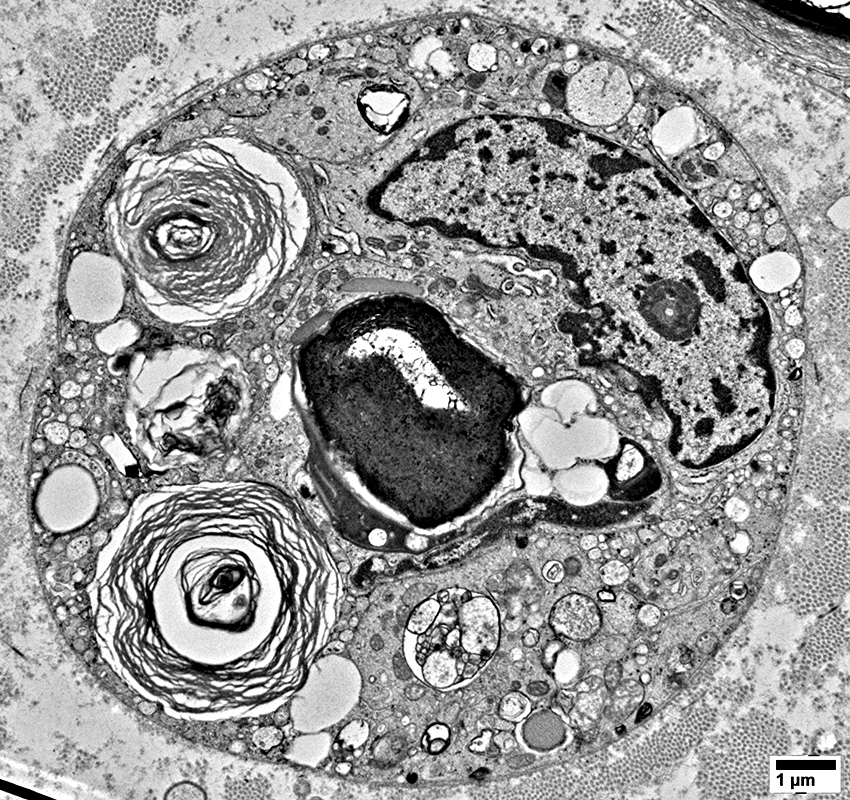

Schwann Cells

Some contain Lipid debris

Myelin Damage: Lipid Droplets & Ovoids in Schwann cells

Myelin Damage: Lipid Droplets & Myelin debris in Schwann cells

Myelin Damage: Lipid Droplets & some Myelin debris in Schwann cells

Lipid Droplets & Myelin debris segregated in different Schwann cell processes

Schwann cells around Axons: Contain Myelin Degradation Products